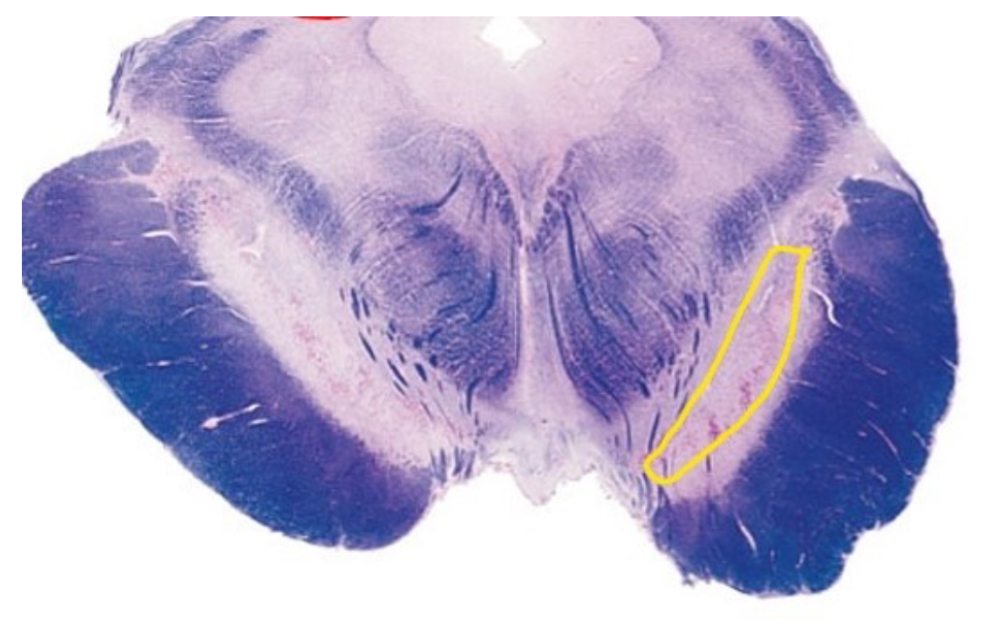

This section is through the ___________________

A

This highlighted structure is _________________

fasiculus cuneatus

The outlined structure is

periaquaducal gray (PAG)